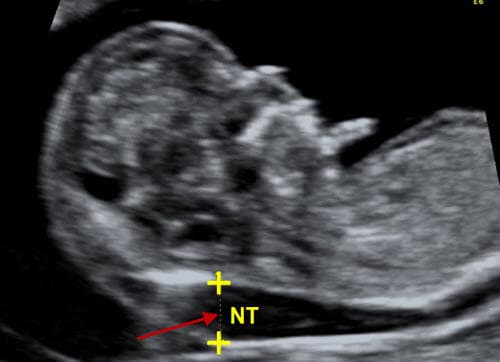

Hội chứng Down (DS) là một rối loạn phát triển gây ra do thừa một nhiễm sắc thể số 21. Nhiễm sắc thể thừa này khiến cho mỗi gene sản sinh ra nhiều protein hơn bình thường, dẫn đến những suy yếu trong cả khả năng nhận thức cũng như phát triển thể chất.

Sở dĩ có nhiễm sắc thể thừa này là do quá trình không phân ly – khi một cặp nhiễm sắc thể số 21 không tách ra trong quá trình hình thành trứng (hay tinh trùng). Khi trứng với tinh trùng bất thường hợp lại để tạo thành phôi, phôi sẽ có đến ba nhiễm sắc thể số 21 thay vì hai như bình thường.

Quá trình không phân ly thường xảy ra ở những phụ nữ lớn tuổi, điều đó có thể giải thích lý do vì sao các bà mẹ 35 tuổi trở lên có nguy cơ sinh con bị hội chứng Down cao hơn. Chẳng hạn, mẹ ở tuổi 30 có nguy cơ sinh con bị hội chứng Down là 1/900. Nhưng tỷ lệ này ở bà mẹ tuổi 35 là 1/350, ở tuổi 40 tăng lên đến 1/100.